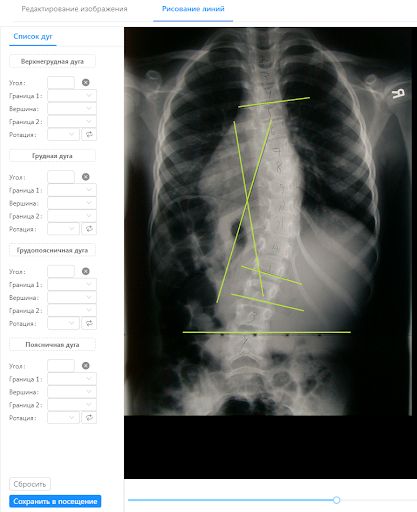

Работа со снимками

Чтобы врач мог более эффективно работать, в системе предусмотрено детальное исследование снимков с помощью специальных инструментов. Это позволяет точно определить проблемную область, поставить диагноз, назначить оптимальное лечение и отследить динамику выздоровления.

В модуль загружается рентген пациента. Изображение кадрируется, появляется возможность менять масштаб рабочей области, поворачивать изображение при необходимости.

Обычно для постановки диагноза специалист измеряет углы и рисует линии на снимке с помощью линейки. Мы же усовершенствовали этот процесс! Теперь линии, помогающие определить угол искривления, рисуются поверх снимка в модуле. Специалист накладывает специальные отрезки, отмечая позвонки, между которыми произошло искривление позвоночника. Система рассчитывает угол Кобба и ротацию позвонков, позволяя определить степень отклонения от нормы. Расчетные данные сохраняются в системе и используются в бланках на изготовление приспособлений для коррекции.

Все снимки хранятся в системе в карточке пациента, а врач в любое время имеет к ним доступ и может сравнивать снимки различной давности. Прямо в системе с помощью «истории снимков» можно увидеть удивительные вещи — безнадежно искривленный позвоночник под действием специальных устройств выпрямляется и возвращается к первоначальному виду.

Как это реализовано?

Загружаемый рентген обрабатывается через canvas, а рисование линий и углов реализовано с помощью D3.js. В интерфейсе специалистам удобно работать как на ПК, так и на персональных планшетах.